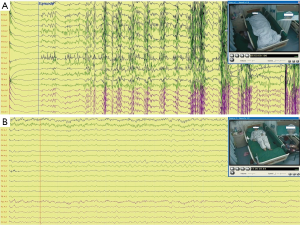

A right-handed 44-year-old woman was diagnosed with epilepsy at the age of 18 years, and over the next 25 years continued to experience multiple focal impaired awareness seizures (FIAS) every month, which mostly evolved into generalized tonic-clonic seizures (GTCS). The patient had a self-reported history of panic attack and anxiety disorder for 10 years, while she had no family history of epilepsy or related disorders. Having therapeutically failed on carbamazepine, phenobarbital and lamotrigine, the patient was referred to our epilepsy center for multi-disciplinary evaluation as a candidate for surgery. Her Hamilton Anxiety Rating Scale (HAM-A) score was 24 admission. Four-day continuous video-EEG monitoring captured three ES, all of right temporal origin (Figure 1A), and two PNES (Figure 1B). According to the patient and her family members, the three ES were typical seizures and two PNES were atypical in terms of semiology.

For ES revealed by video-EEG, the patient experienced a sudden loss of consciousness during sleep, followed by oral and right limb automatism, stiffening of body (tonic phase) for 10–20 s, and subsequent jerking of the extremities (clonic phase) for another 30–40 s. Low-voltage fast activity occurred on EEG and represented the initial ictal pattern. For PNES, the patient reported indescribable anxiety and discomfort, then gradually developed repetitive head nodding or side-to-side shaking with preserved consciousness. Eye closure and bilateral limb movement were also observed during the whole episode of PNES, which lasted for over 10 min. Ictal epileptiform discharges were absent.